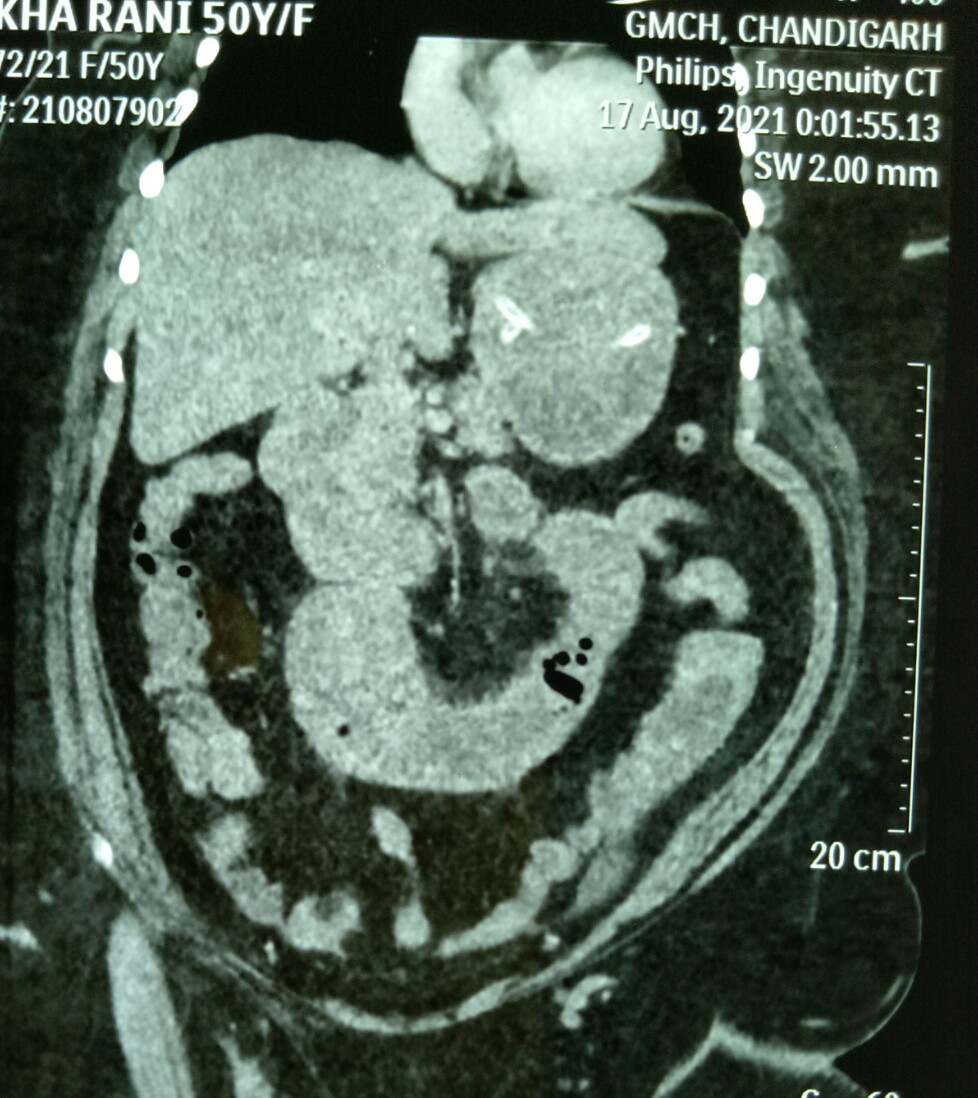

Rekha Rani, 45 years old female, presented with the diagnosis of gastric outlet obstruction (GOO) (on ultrasound!) at Shalley hospital, and was referred to Chandigarh GMCH. There a CT scan showed high SBO (in jejunum), pneumobilia and a stone impacted in proximal jejunum causing the obstruction (Rigler’s triad). At laparotomy, an enterotomy was done to remove the stone and enterotomy closed.